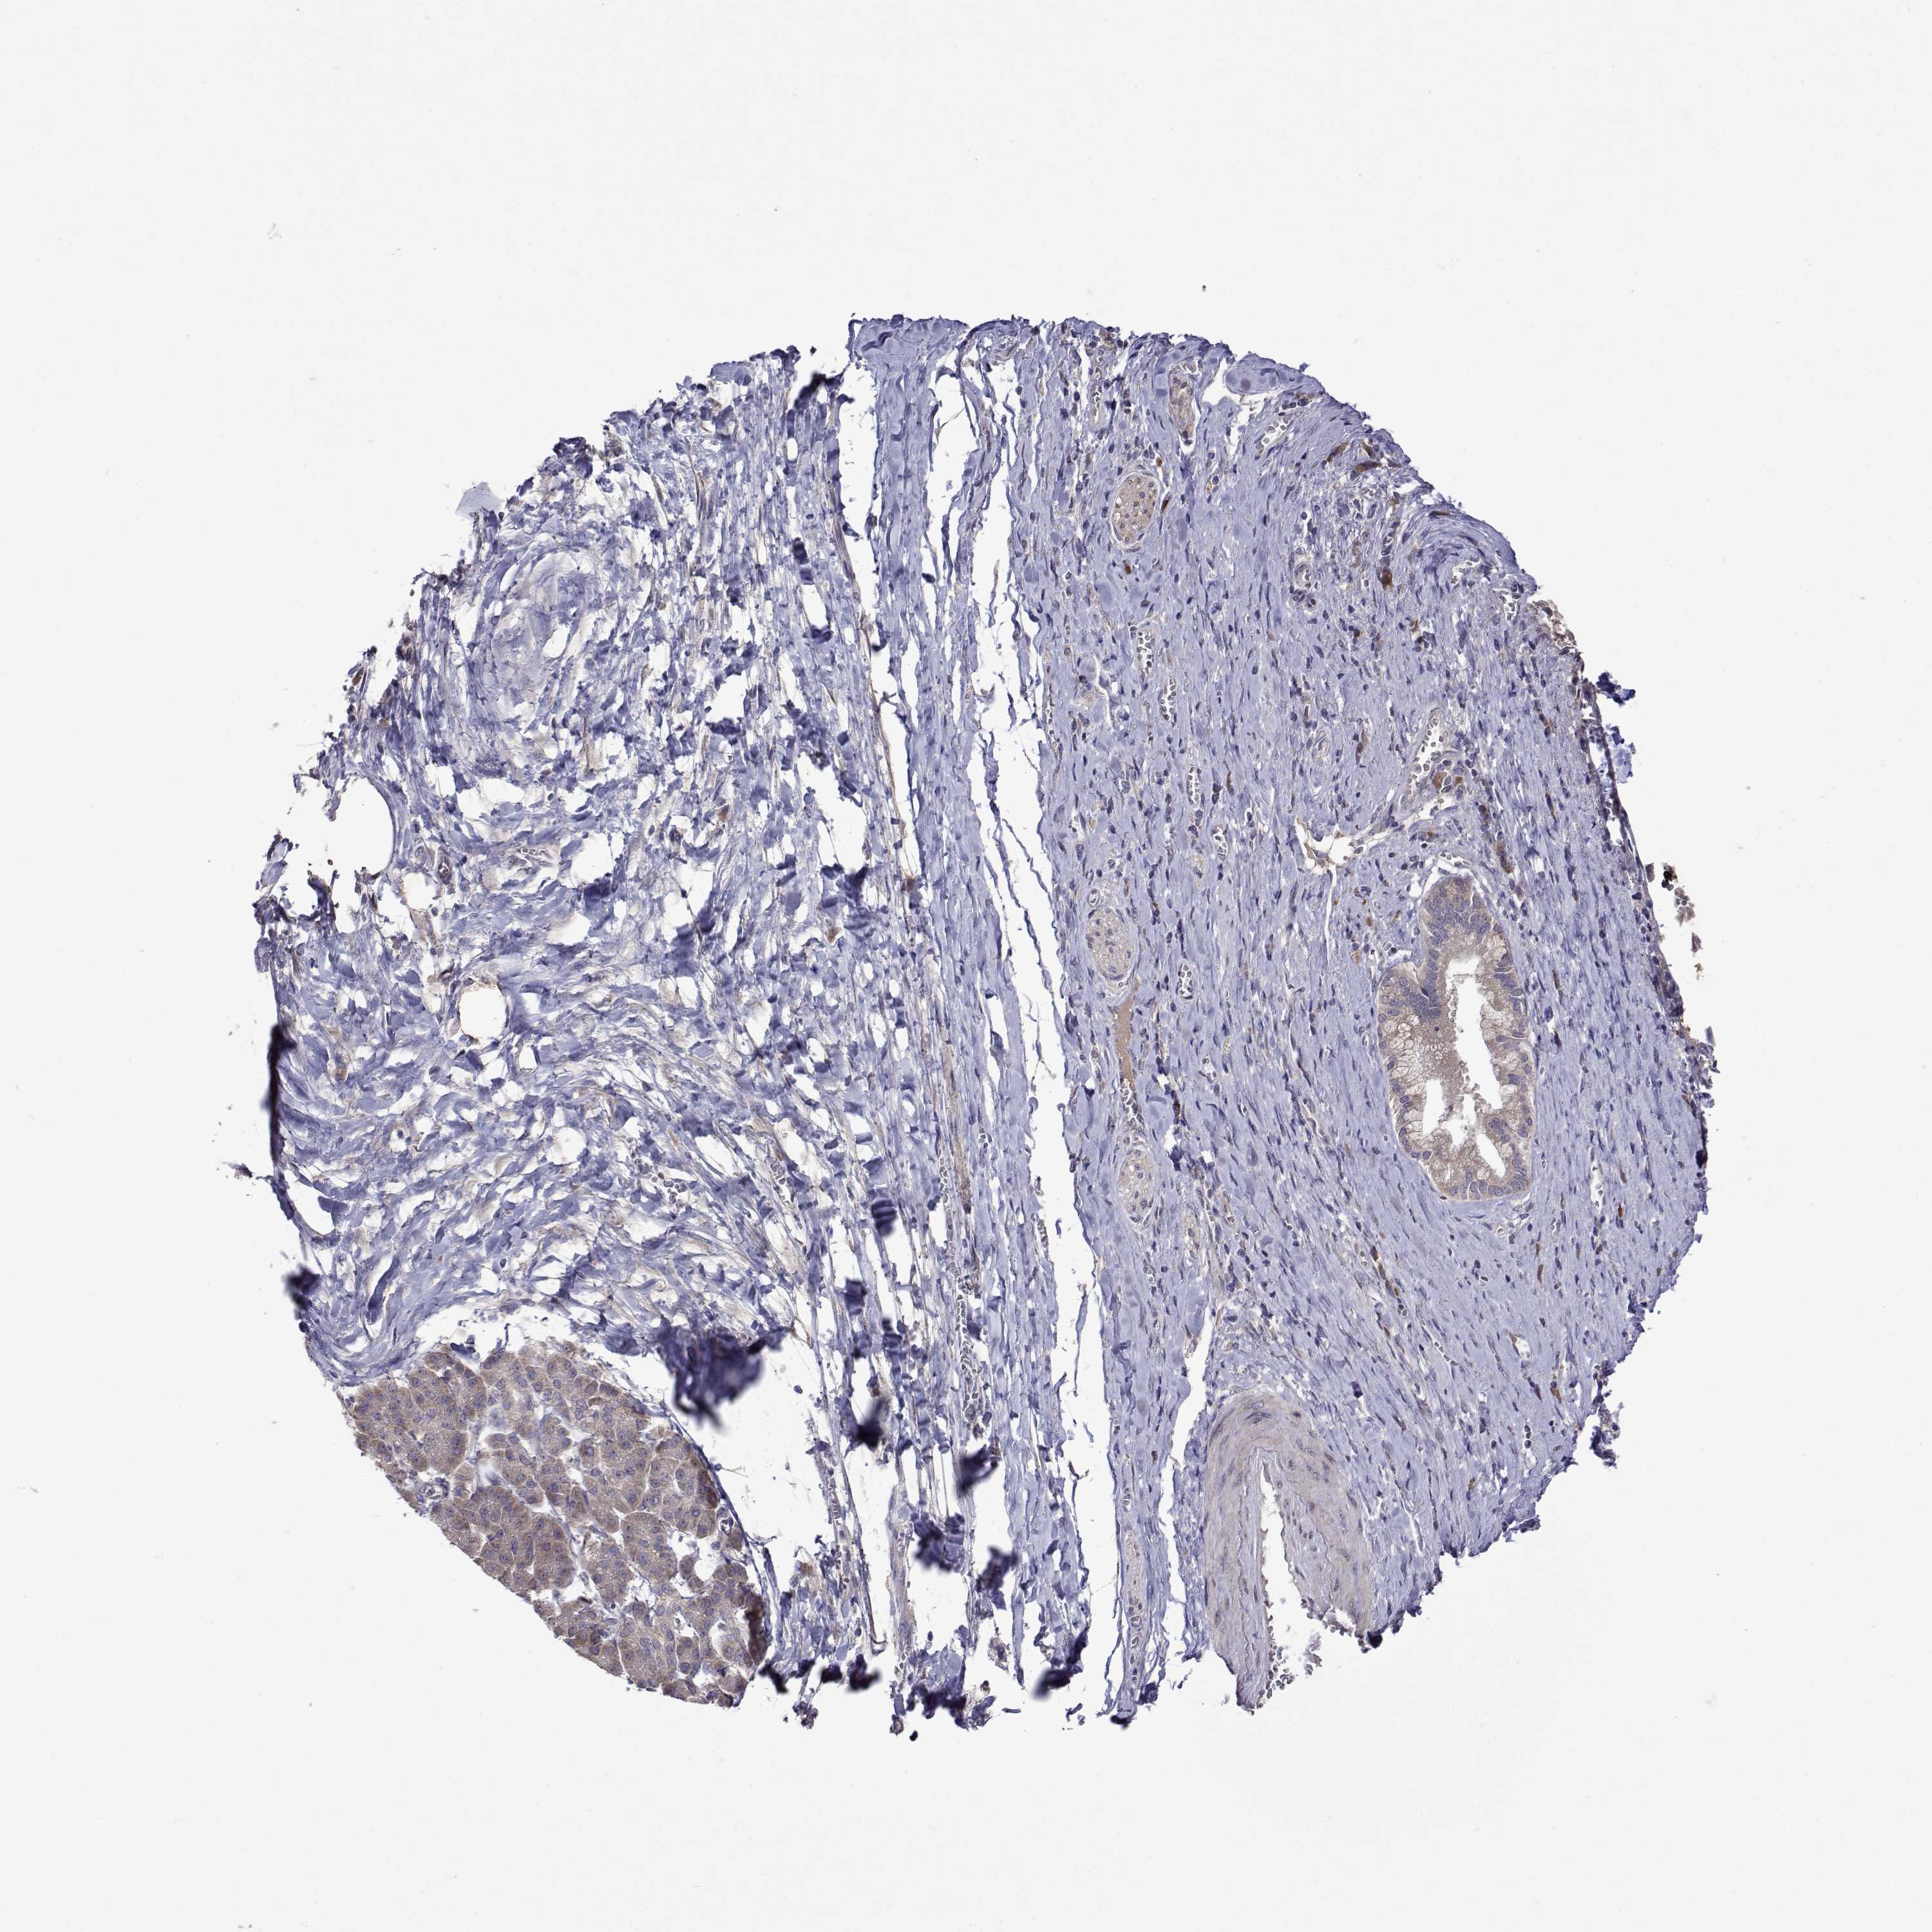

PANCREATIC CANCER - Protein expressioni

A mouse-over function shows sample information and annotation data. Click on an image to view it in a full screen mode. Samples can be filtered based on level of antibody staining by selecting one or several of the following categories: high, medium, low and not detected. The assay and annotation is described here.

Note that samples used for immunohistochemistry by the Human Protein Atlas do not correspond to samples in the TCGA dataset.

Antibody stainingi

Antibody staining in the annotated cell types in the current human tissue is reported as not detected, low, medium, or high, based on conventional immunohistochemistry profiling in selected tissues. This score is based on the combination of the staining intensity and fraction of stained cells.

Each image is clickable and will lead to virtual microscopy that enables deeper exploration of all samples and also displays staining intensity scores, fraction scores and subcellular localization as well as patient and tissue information for each sample.

Antibody HPA051181

Antibody HPA061454

Antibody CAB069406

Staining

High

Medium

Low

Not detected

Intensity

Strong

Moderate

Weak

Negative

Quantity

>75%

75%-25%

<25%

None

Location

Nuclear

Cytoplasmic/membranous

Cytoplasmic/membranous,nuclear

Adenocarcinoma, NOS